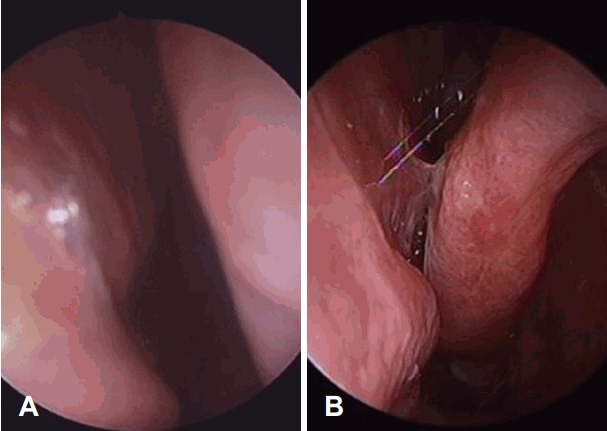

환자는 수술 후 12일째 내원 시 수술 전에 있던 코막힘이 호전되어 편안하게 지낸다고 하였다. 내시경 소견상 수술 전부터 있던 좌측 하비갑개의 함몰은 여전히 있었으나 비중격 만곡은 해소되어 곧게 유지되고 있었고(Fig. 4A), 특별한 합병증 없어 이후 경과 관찰 없이 지내기로 하였다.

Endoscopic view of left nasal cavity. A : Endoscopic examination of left nasal cavity at postoperative day 12 of septoplasty. B: Endoscopic examination of left nasal cavity after inferior turbinate medialization.

하비갑개 내향 절골술 시행 후 10일 뒤 비강 내 소견상 하비갑개는 수술 전에 비해 안쪽으로 편위된 상태로 유지되었고(Fig. 4B), 숨 쉴 때 코에 느껴지는 불편한 개방감은 다소 호전되었으나 호흡 시 발생하는 목 통증은 호전되지 않았다. 수술 후 41일 째에 외래에 내원하였을 때는 우측 코의 저항감이 새롭게 발생하였고 좌측 코의 개방감 또한 재발하여 그로 인한 심한 불편감을 호소하였다. Empty Nose Syndrome 6-Item Questionnaire (ENS6Q)를 시행하였으며 코가 휑하게 뚫려있는 느낌이 4점으로 심하게 느껴진다고 호소하였으나 좌측 하비갑개 아래를 cotton으로 막고 20분 뒤 증상을 비교했을 때는 이러한 개방감이 2점으로 호전되었다. 이에 대한 치료적 시도로 일시적인 하비갑개 용적 증가 및 하비갑개 점막의 회복 촉진을 위해 외래에서 환자의 정맥혈을 채혈하여 좌측 하비갑개에 주입하였다. 전주 정맥(antecubital vein)에서 약 4 cc 정도의 정맥혈을 채취하고 하비갑개 부분에 1:200000 epinephrine - lidocaine pledget으로 표면마취를 시행한 뒤, 채취한 혈액을 하비갑개 전후방에 21G 주사침을 이용하여 천천히 주입하였다. 환자가 느끼는 감각 개선을 위해 LyricaⓇ cap (pregabalin; Viatris Korea, Seoul, Korea) 75 mg 경구약을 처방하여 하루 1회 복용하도록 하였으며 점막 팽창을 위한 RectogesicⓇ ointment를 다시 처방하여 좌측 비강 내에 도포하도록 하였다. 이러한 처치에도 불구하고 개방감과 호흡 연관 목 통증 증상은 유지되었으나 솜으로 좌측 비강을 막으면 일상생활이 가능하여 우선 외래에서 경과 관찰 시행하기로 하였으며, 추후 환자 희망시 좌측 비중격 보강 수술을 시행할 예정이다.